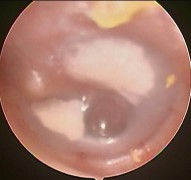

Ảnh 14 MN thủng MSBA. 1906298068 |